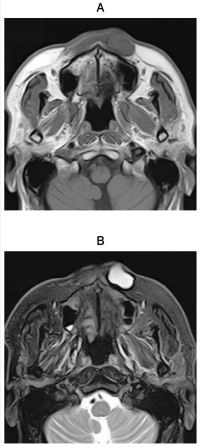

70歳の男性。鼻下部の無痛性の腫脹を主訴として来院した。10年以上前から自覚しており、緩徐に増大してきたという。初診時のMRI T1強調像と脂肪抑制T2強調像及び超音波検査の画像を示す。

考えられるのはどれか。1つ選べ。